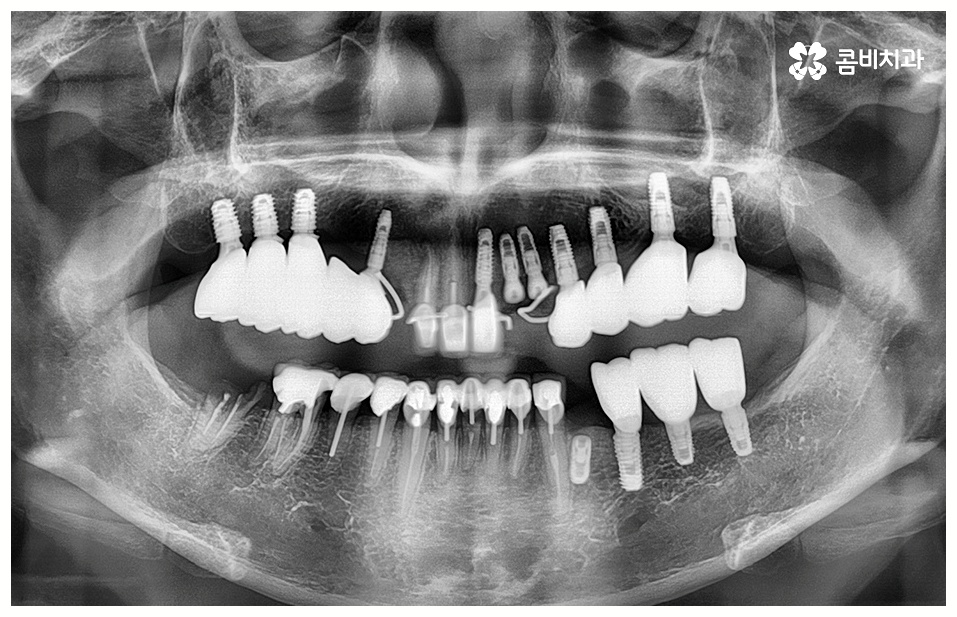

임플란트 시술을 받을 때 많은 분들이 궁금해 하시는 것 중 하나가 임플란트 치료기간 그리고 수명에 대한 것일 텐데요, 먼저 기간은 대략적으로 3~6개월 정도 걸린다고 알려져 있으나 환자마다 잇몸뼈 상황이나 전체적인 건강 상태 및 회복력이 다르기 때문에 환자분들에 따라 다르게 적용되고 있는 부분이고 그에 따라 임플란트 치료기간 또한 달라질 수 있습니다.

예를 들어서 잇몸뼈가 튼튼하다면 발치 후 즉시 임플란트 식립 시술을 할 수 있어서 임플란트 치료기간 이 줄어들고 보다 간편한 수복이 가능할 것이나 주변 잇몸에 염증이 남아있어서 먼저 치료를 해야 하거나 바탕이 되는 잇몸뼈의 밀도, 높이 등이 부족하여 보충이 필요한 경우에는 뼈이식 과정을 우선 진행해야 하기 때문에 임플란트 치료기간 이 길어질 수 있어요.

임플란트 치료는 자신의 자연 치아를 대신해 오랫동안 쓸 수 있도록 장기적인 안정성을 추구하는 것이 중요하기 때문에 최초의 진단과 치료 계획을 꼼꼼하게 세우는 것이 필수라고 할 수 있어요.

또한 풍부한 임상 경험과 노하우를 가진 숙련된 의료진, 다각적이고 체계적인 분석을 할 수 있는 3D CT 와 같은 정밀 분석 장비를 갖추고 보다 안정성이 검증된 정품 재료의 사용 여부 등을 잘 체크해야 할 거예요.